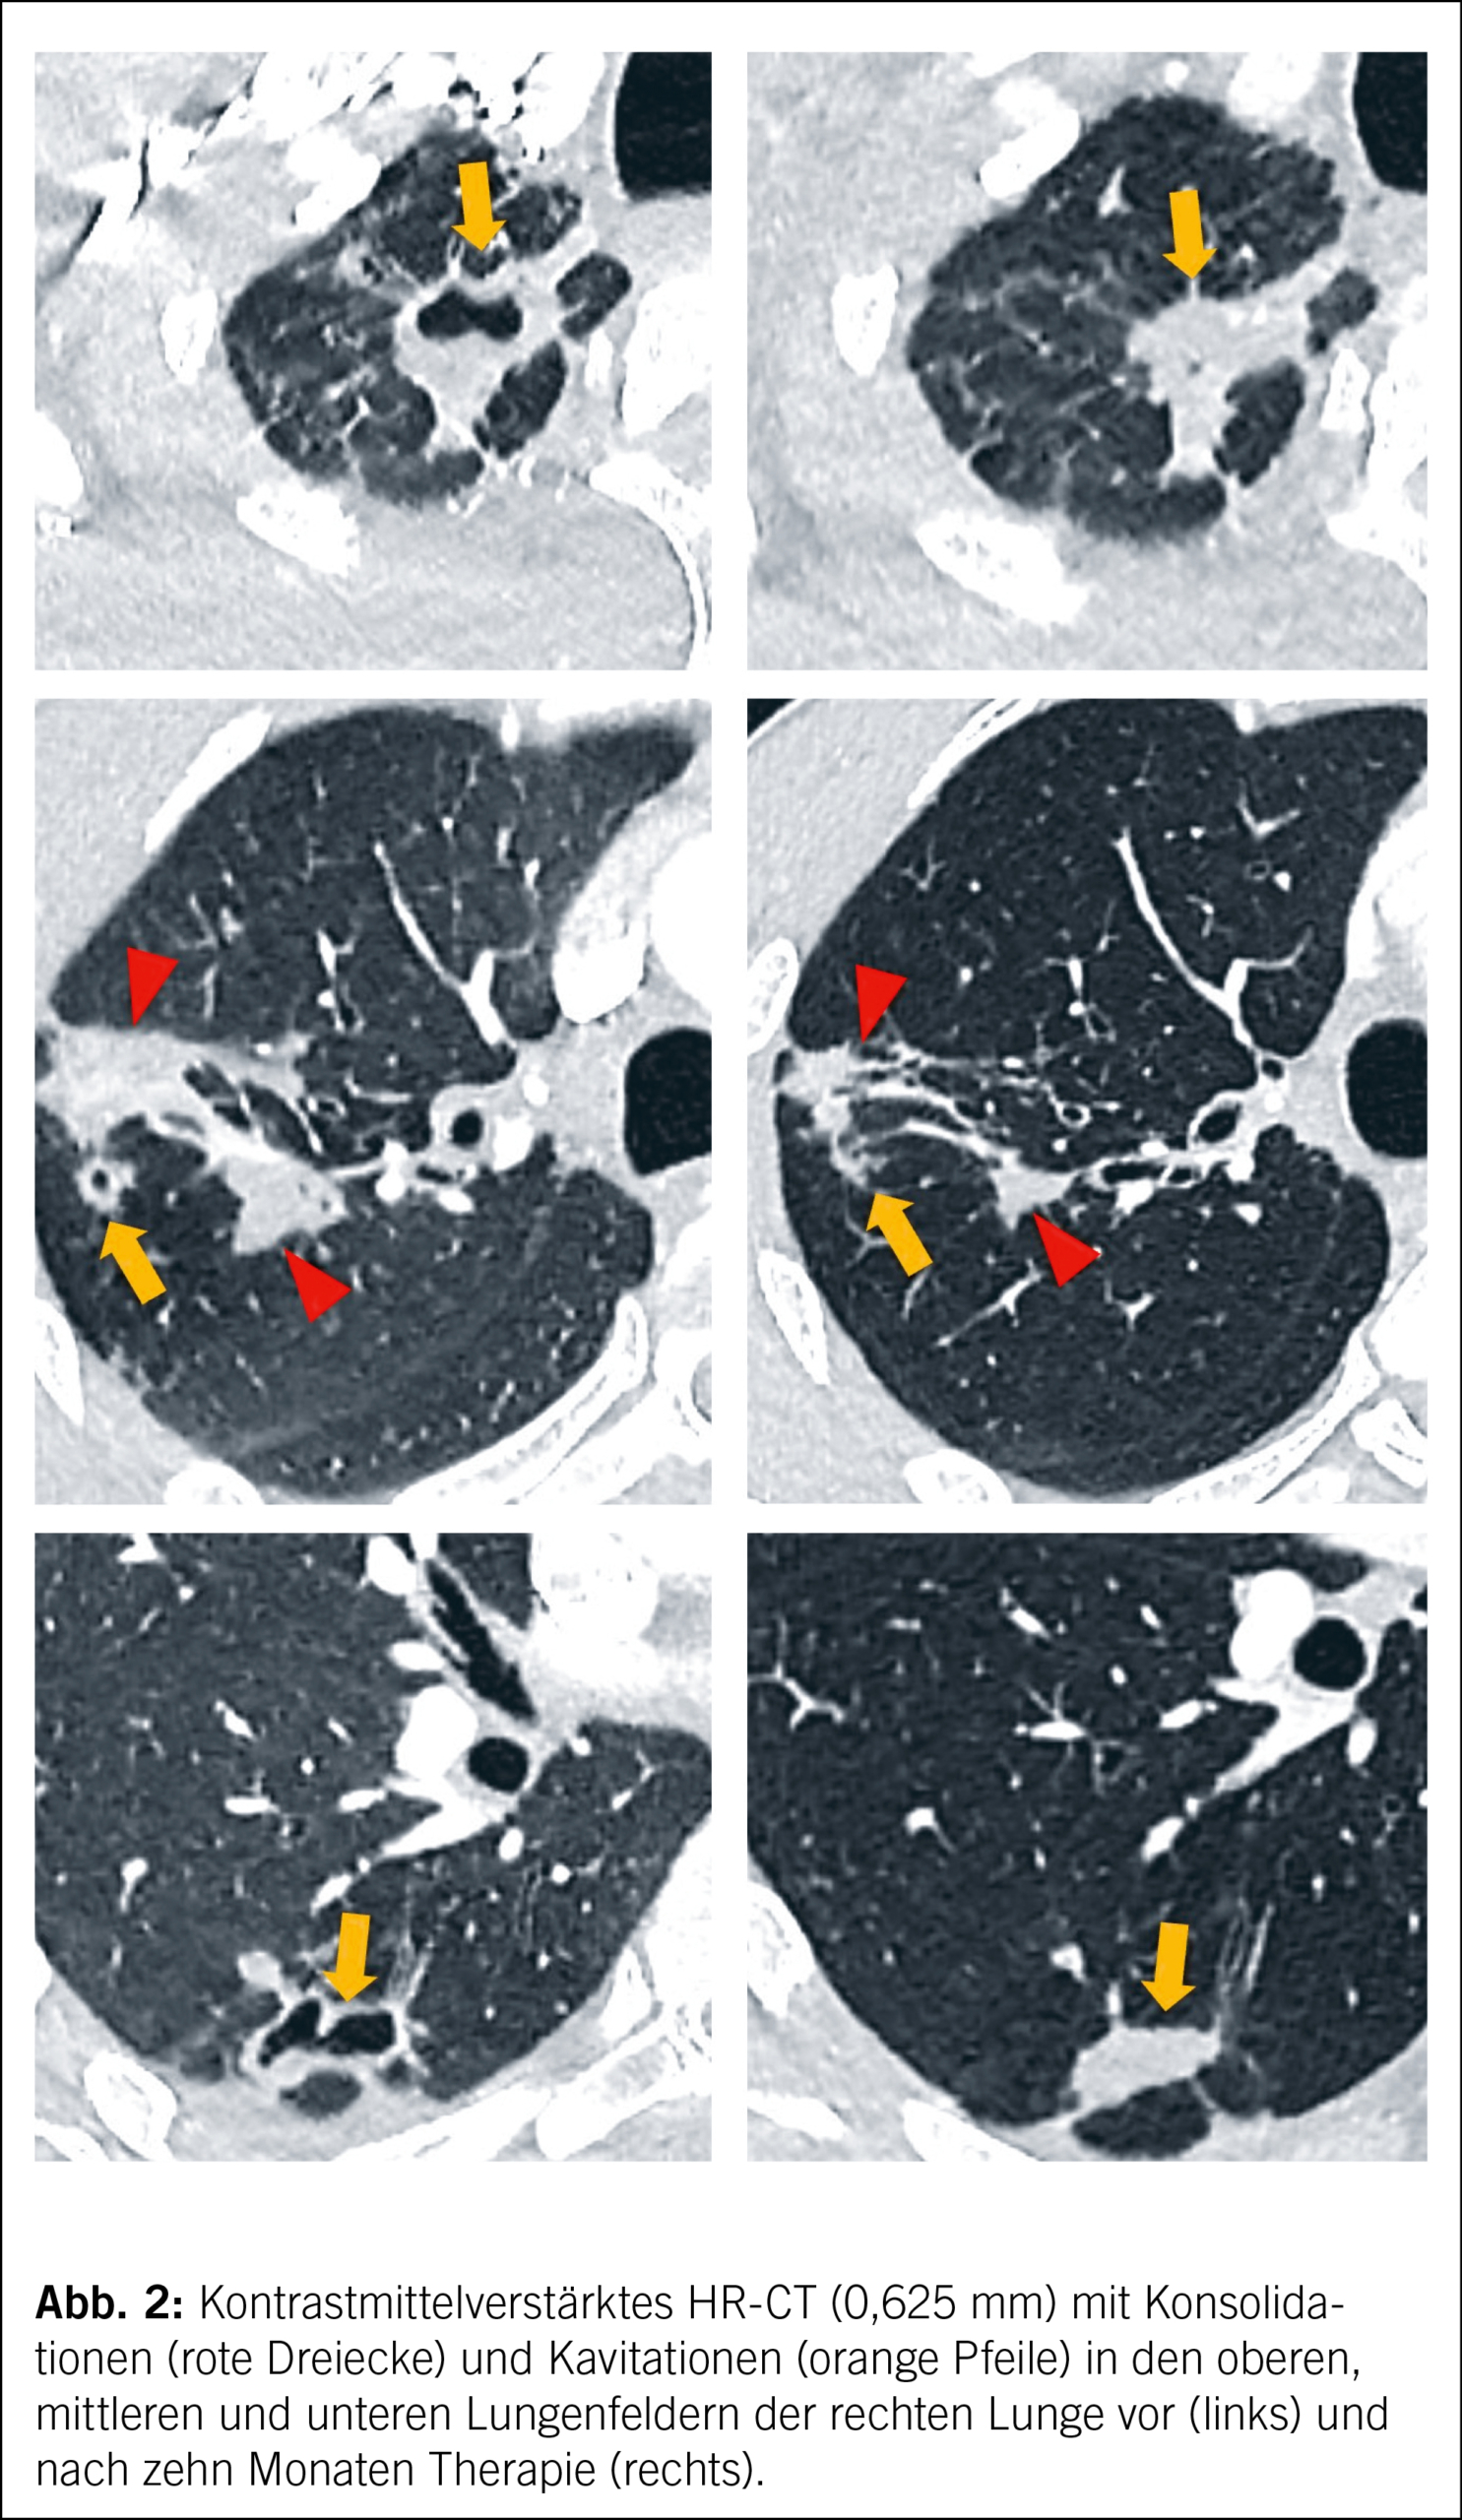

Der Patient präsentierte sich bei Eintritt kachektisch mit einem BMI von 17,8 kg/m2, die pulmonale Auskultation ergab abgeschwächte Atemgeräusche über dem rechten Mittelfeld. Computertomographisch kamen postspezifische Veränderungen im rechten Ober- und Unterlappen mit ausgedehnten Konsolidierungen und mehreren Kavernen mit Anschluss an das Bronchialsystem zur Darstellung (Abb. 1).

Der Patient war über fünf Wochen unter aerogener Isolation hospitalisiert, bis die geeignete Therapie gestartet werden konnte. Nach interdisziplinärer Besprechung am Mykobakterien-Board, unter Beizug von Experten des deutschen Referenzzentrums für Mykobakterien sowie konsiliarisch der Thoraxchirurgie, fiel die Entscheidung auf eine empirische Therapie mit Linezolid p.o., Cycloserin p.o., Amikacin i.v. und Meropenem plus Clavulansäure i.v. (mangels Verfügbarkeit eines Clavulansäure-Monopräparats verabreichten wir Co-Amoxicillin plus Meronem). Cycloserin musste aus Japan bzw. den USA bestellt werden, was den Therapiestart um zwei Wochen verzögerte. Drei Wochen nach Beginn der Behandlung zeigte sich ein erfreuliches Ansprechen mit komplett sistiertem Husten, Afebrilität und einer Gewichtszunahme von 5 kg. Der Patient wurde zur Fortsetzung der Therapie unter weiterhin strenger Isolationsmassnahme in eine andere Klinik verlegt. Unter Therapie erfolgten zum Zeitpunkt sechs, sieben und acht Wochen erneute Sputumkontrollen, die mikroskopisch und kulturell negativ blieben. Nach zweimonatiger Behandlung wurde eine Verlaufs-Computertomographie durchgeführt, die eine Resolution der pulmonalen Kavernen zeigte und das klinische Therapieansprechen radiologisch bestätigte (Abb. 2).